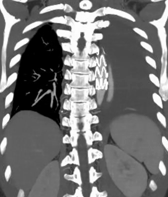

患者盆腔出血病情稳定一周后,经严格控制血压、稳定心率、卧床制动等治疗后,复查主动脉CTA提示主动脉夹层较前有所进展。主动脉疾病MDT团队——包括心血管外科、介入医学科、麻醉科、重症医学科(因患者合并骨盆骨折、血尿,还邀请了肾内科、泌尿外科、四肢关节骨科)等多学科专家进行了深入讨论,考虑该患者Stanford B型主动脉夹层累及范围广泛,如同体内“不定时炸弹”,具有限期手术干预指征,需要及时精确拆除。

△注:主动脉内膜呈螺旋形撕裂,夹层形成,随时可能因主动脉破裂、脏器缺血坏死等而危及生命。

经过周密计划,该科室制定了分阶段杂交手术方案:心血管外科先通过2处5cm的手术切口行颈动脉—锁骨下动脉搭桥,建立血流通路;接着介入科团队接力,通过3处不超过1cm的微创伤口完成胸主动脉夹层腔内覆膜支架隔绝术,并用血管塞精准封堵左锁骨下动脉起始段以避免术后支架内漏。

△注:支架精准定位,稳定释放,成功以“人工血管”将主动脉破口隔绝。

△注:患者出院后定期我科门诊复查,术后2月复查提示支架完美重建胸主动脉血管通路,原夹层内部基本血栓化,未发现相关并发症。